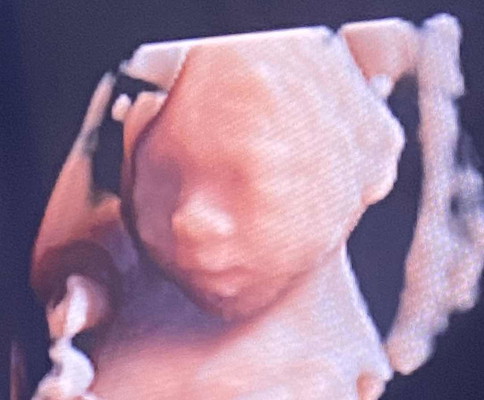

ตอนนี้24+3wk แล้วค่า นน.700 กรัม

ดั้งมาแต่น้อยเลยลูก😍